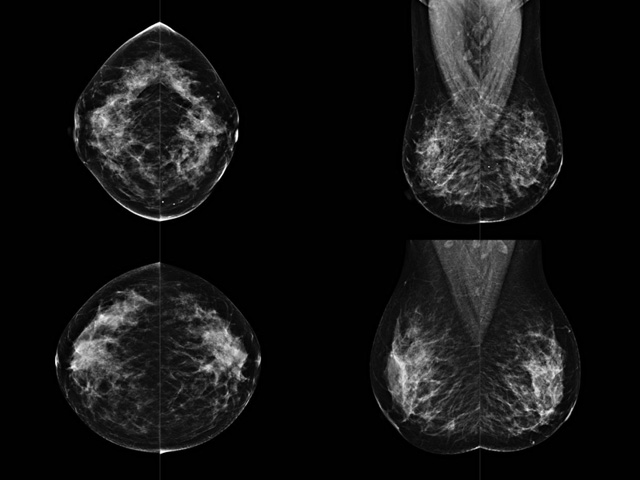

乳房檢查時(shí)候要注意一些細(xì)節(jié),需要更深入的了解這樣才能使檢查更準(zhǔn)確。乳腺DR是乳腺癌的篩查診斷工具設(shè)備。是乳房方面檢查的重要影像方法。它可以臨床檢查出早期的乳腺癌??梢耘袛嗔夹詯盒?。因?yàn)樗梢詸z查出早期的病變。對良性惡性檢查的準(zhǔn)確率達(dá)到90%以上。發(fā)病高峰年齡為45歲到54歲。50歲檢查出來乳腺癌病患,可以讓死亡率下降3成。所以30-40歲女性每年做一次乳腺DR檢查。40歲以上就一年兩次。如果家族史有乳腺癌的30歲以下也需要做檢查。清晰顯示乳腺各層組織嚴(yán)重的乳腺增生,乳腺炎,乳腺外傷也建議1年檢查一次。極大提高了早期乳腺癌的敏感度和診斷率。

大角度、高質(zhì)量的乳腺檢查,可以讓女性帶來身體健康安全。為醫(yī)生提供了高清影像數(shù)據(jù)。乳腺檢查時(shí)候各個(gè)部位影像顯示出來。白色乳腺導(dǎo)管跟纖維結(jié)締組織。模糊的是脂肪。病變一般是不透明的白色。有需要放大來檢查。乳腺DR沒有重疊偽影。輻射劑量更少。因?yàn)槿橄侔┌l(fā)病每年都有所提高,對女性都造成了嚴(yán)重的身體健康危害。早做檢查早治療是不可忽視的舉措。可以大大的降低死亡率。保證身體健康。一般檢查避開經(jīng)期,來完7天左右是最佳的檢查時(shí)間。絕經(jīng)的女性就沒有要求。孕婦不參加乳腺DR檢查, 6個(gè)月內(nèi)準(zhǔn)備妊娠的婦女也不宜行此檢查。